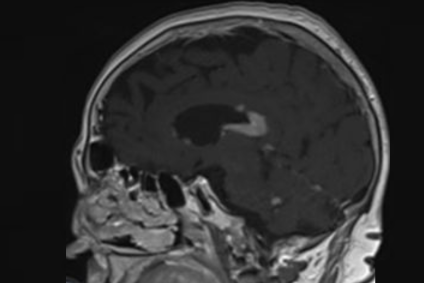

Con una presentación clínica variable, incluye déficits neurológicos focales, alteraciones cognitivas, cambios en el comportamiento y, en algunos casos, síntomas de hipertensión intracraneal como náuseas y vómitos. En consiguiente, su diagnóstico requiere un alto grado de sospecha clínica y el uso de herramientas avanzadas como la resonancia magnética (functional magnetic resonance imaging, fMRI, en inglés). Siguiendo esta línea, las principales características del linfoma cerebral son las siguientes:

- Localización de las lesiones: Frecuentemente, afecta estructuras profundas como el cuerpo calloso y los ganglios basales.

- Patrón de crecimiento: Infiltración angiocéntrica que se extiende a lo largo de los vasos sanguíneos.

- Diagnóstico por imagen: Lesiones homogéneamente realzadas con contraste y edema leve.

Como ya adelantamos previamente, el linfoma cerebral se diagnostica mediante resonancia magnética con gadolinio y, en casos específicos, análisis de líquido cefalorraquídeo para detectar células malignas. Su tratamiento se basa en quimioterapia de altas dosis con metotrexato, complementada con radioterapia o trasplante autólogo de células madre, aunque las recaídas son frecuentes.